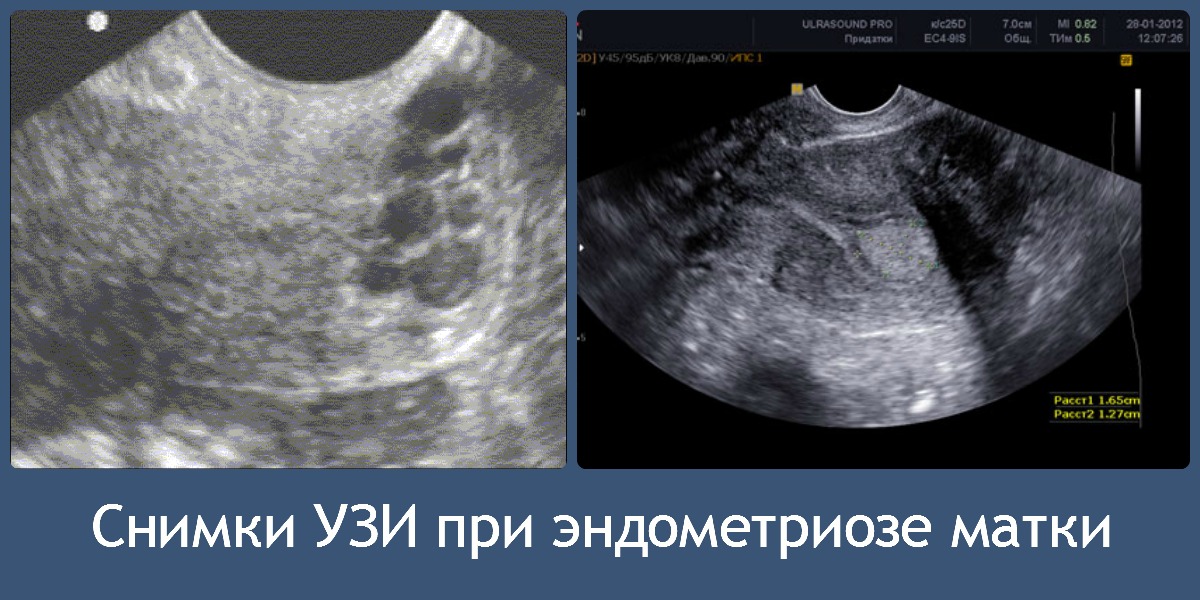

Врачи отмечают, что ультразвуковое исследование является важным инструментом в диагностике эндометриоза. На УЗИ можно выявить характерные признаки, такие как кисты яичников, которые могут содержать эндометриоидную ткань. Специалисты подчеркивают, что наличие гиперэхогенных образований и утолщение стенок матки также могут указывать на это заболевание. Важно, что УЗИ позволяет не только обнаружить изменения в репродуктивных органах, но и оценить степень распространения эндометриоза. Врачи рекомендуют проводить ультразвуковое исследование при наличии симптомов, таких как болезненные менструации или хроническая тазовая боль, чтобы своевременно начать лечение и предотвратить возможные осложнения.

Говоря о таком параметре, как эхопризнаки эндометриоза стоит отметить, что показатель может существенно отличаться в зависимости от стадии цикла. Так, на его первой стадии такое исследование не покажет буквально ничего, поскольку этот недуг никогда не классифицировался как гистологическая находка. На более поздних стадиях выявить проблему уже можно, и тут эхография воспринимается как основной метод.

Основные эхопризнаки поддаются следующей классификации:

- асимметрия толщины стенок матки. Как правило, единицей измерения отклонений выступают миллиметры, но в запущенных случаях речь идёт уже о сантиметрах;

- увеличение матки. Иногда рост достигает параметров, характерных для 6 недели беременности.

Если такая диагностика приведёт к обнаружению эндометриоза, то УЗИ покажет следующие отклонения от нормы:

- образования узлового типа;

- ассиметричность стенок матки;

- нарушения в структуре эндометрия.

Эти показатели помогают врачу определить, от какого конкретно заболевания страдает пациентка. Если речь идёт о поражении яичников, то признаки эндометриоза на УЗИ будут следующими:

- округлые образование, локализованные позади или в стороне от матки;

- мелкоточечная структура внутренних тканей. Этот фактор будет виден особенно отчетливо;

- кроме того во время исследования будет видно образования очагового типа;

- увеличенные эхопризнаки миометрия.

Если эндометриоз уже присутствует в организме, на экране УЗИ аппарата будут четко видны характерные признаки, такие как увеличение размера матки и разная плотность мышечного слоя на разных участках. Гинеколог также сможет увидеть отсутствие или наличие капсулы во внутреннем слое матки.